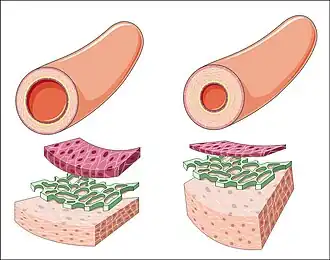

Proceso de remodelado arterial en la hipertensión arterial | ||

La hipertensión arterial, de manera silente, produce cambios en el flujo sanguíneo, a nivel macro y microvascular, causados a su vez por disfunción de la capa interna de los vasos sanguíneos y el remodelado de la pared de las arteriolas de resistencia, que son las responsables de mantener el tono vascular periférico. Muchos de estos cambios anteceden en el tiempo a la elevación de la presión arterial y producen lesiones orgánicas específicas.

Al transcurrir los años y según los aspectos de la enfermedad, el número de fibras de colágeno en las paredes arteriales aumenta, haciendo que los vasos sanguíneos se vuelvan más rígidos. Al reducirse así la elasticidad, el área seccional del vaso se reduce, creando resistencia al flujo sanguíneo y como consecuencia compensadora, se aumenta la presión arterial.

Arterias periféricas

- Disfunción endotelial crónica, con vasoconstricción inapropiada, liberación de especies reactivas de oxígeno, inflamación, aumento de actividad protrombótica y reducción de la fibrinólisis.

- Remodelado parietal y estrechamiento luminal a expensas de redistribución de músculo liso de la túnica media arterial.